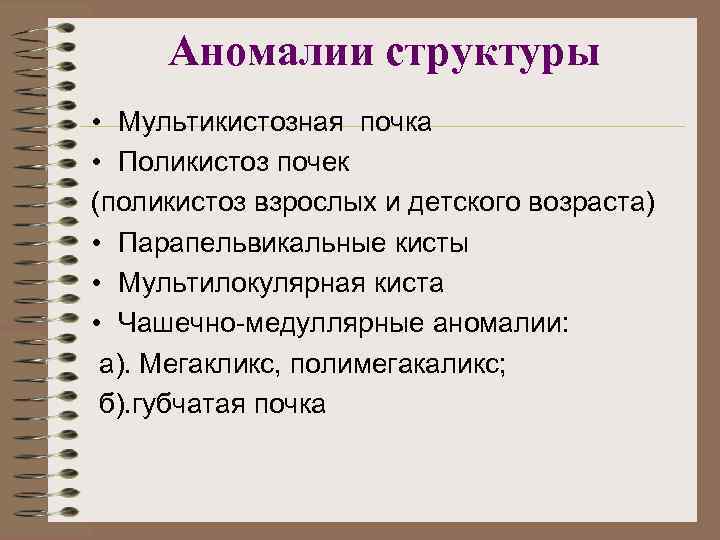

Аномалии структуры • Мультикистозная почка • Поликистоз почек (поликистоз взрослых и детского возраста) • Парапельвикальные кисты • Мультилокулярная киста • Чашечно-медуллярные аномалии: а). Мегакликс, полимегакаликс; б). губчатая почка